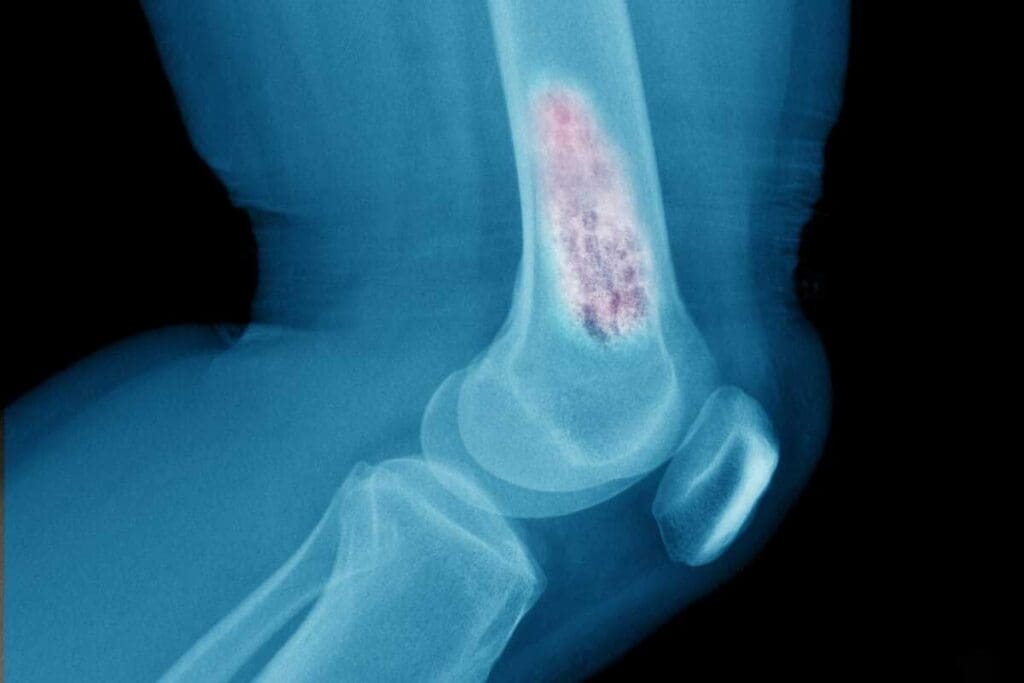

Diagnostic Process and Workup

To diagnose Ewing sarcoma, doctors use many tests. These include X-rays, MRI, CT scans, and PET scans. They help find out the tumor’s size, where it is, and if it has spread.

A biopsy is also needed to confirm the diagnosis. The biopsy sample is looked at under a microscope. This helps spot the small, round, blue-staining cells that are a sign of this cancer.

Tumor Location and Size

The tumor’s location and size are key. Tumors in the pelvis or spine often have a worse prognosis. This is compared to tumors in other parts of the body.

Tumor size matters a lot. Bigger tumors are harder to treat. They also have a higher chance of coming back.